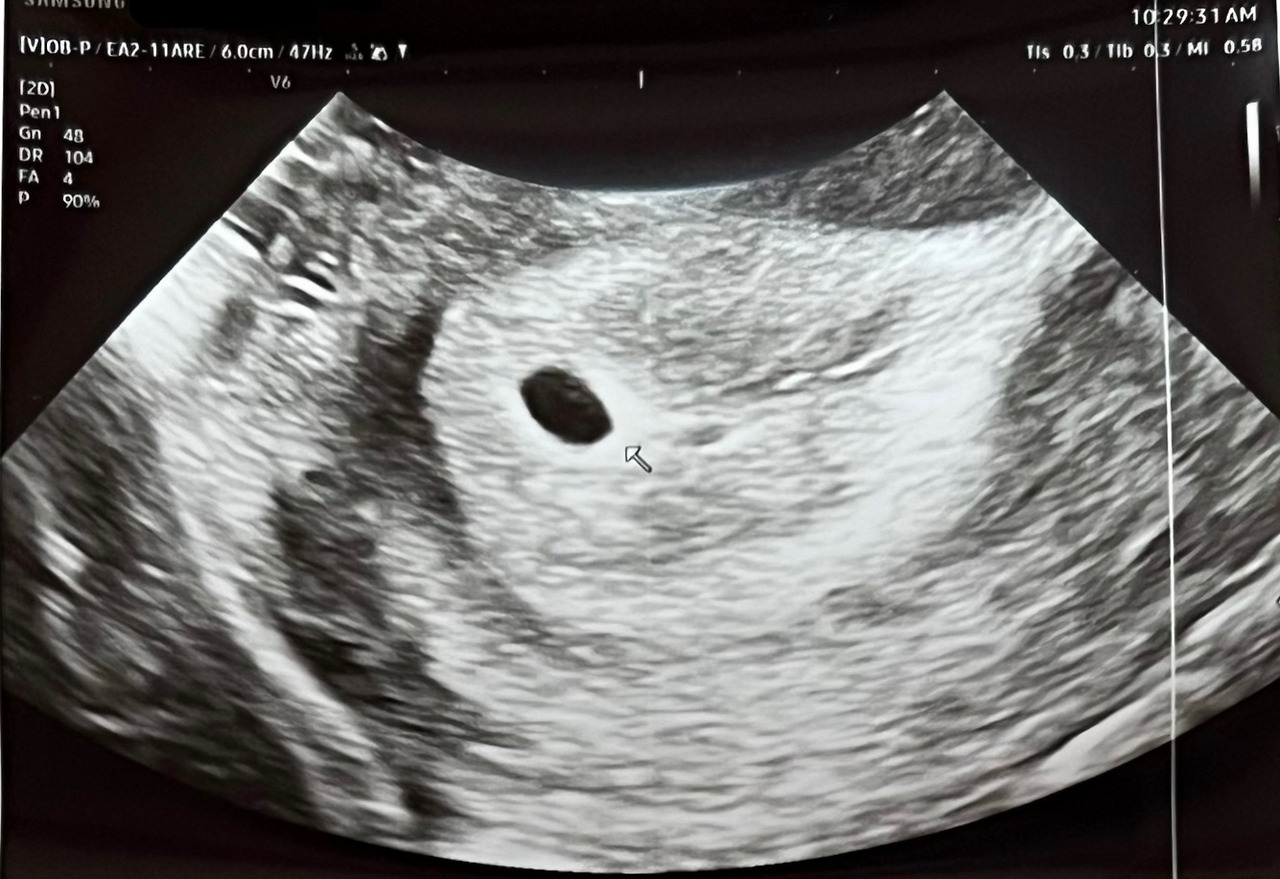

임신테스트기에 아주 진한 빨간색 두 줄이 생겼고, 나는 처음으로 산부인과를 찾았다. 의사 선생님이 "이게 아기집이에요"라고 말씀하셨다. 그 말을 들은 순간, 나는 '이제 임신이 된 거구나'하고 안심했다. 하지만 그건 단지 시작이었다. 아기집이 보인 뒤엔 난황이 보여야 하고, 그다음엔 아기가 있어야 하며 그다음엔 심장소리를 들어야 한다. 마치 게임 퀘스트를 깨듯, 다음 단계를 통과해야만 하는 여정이었다.